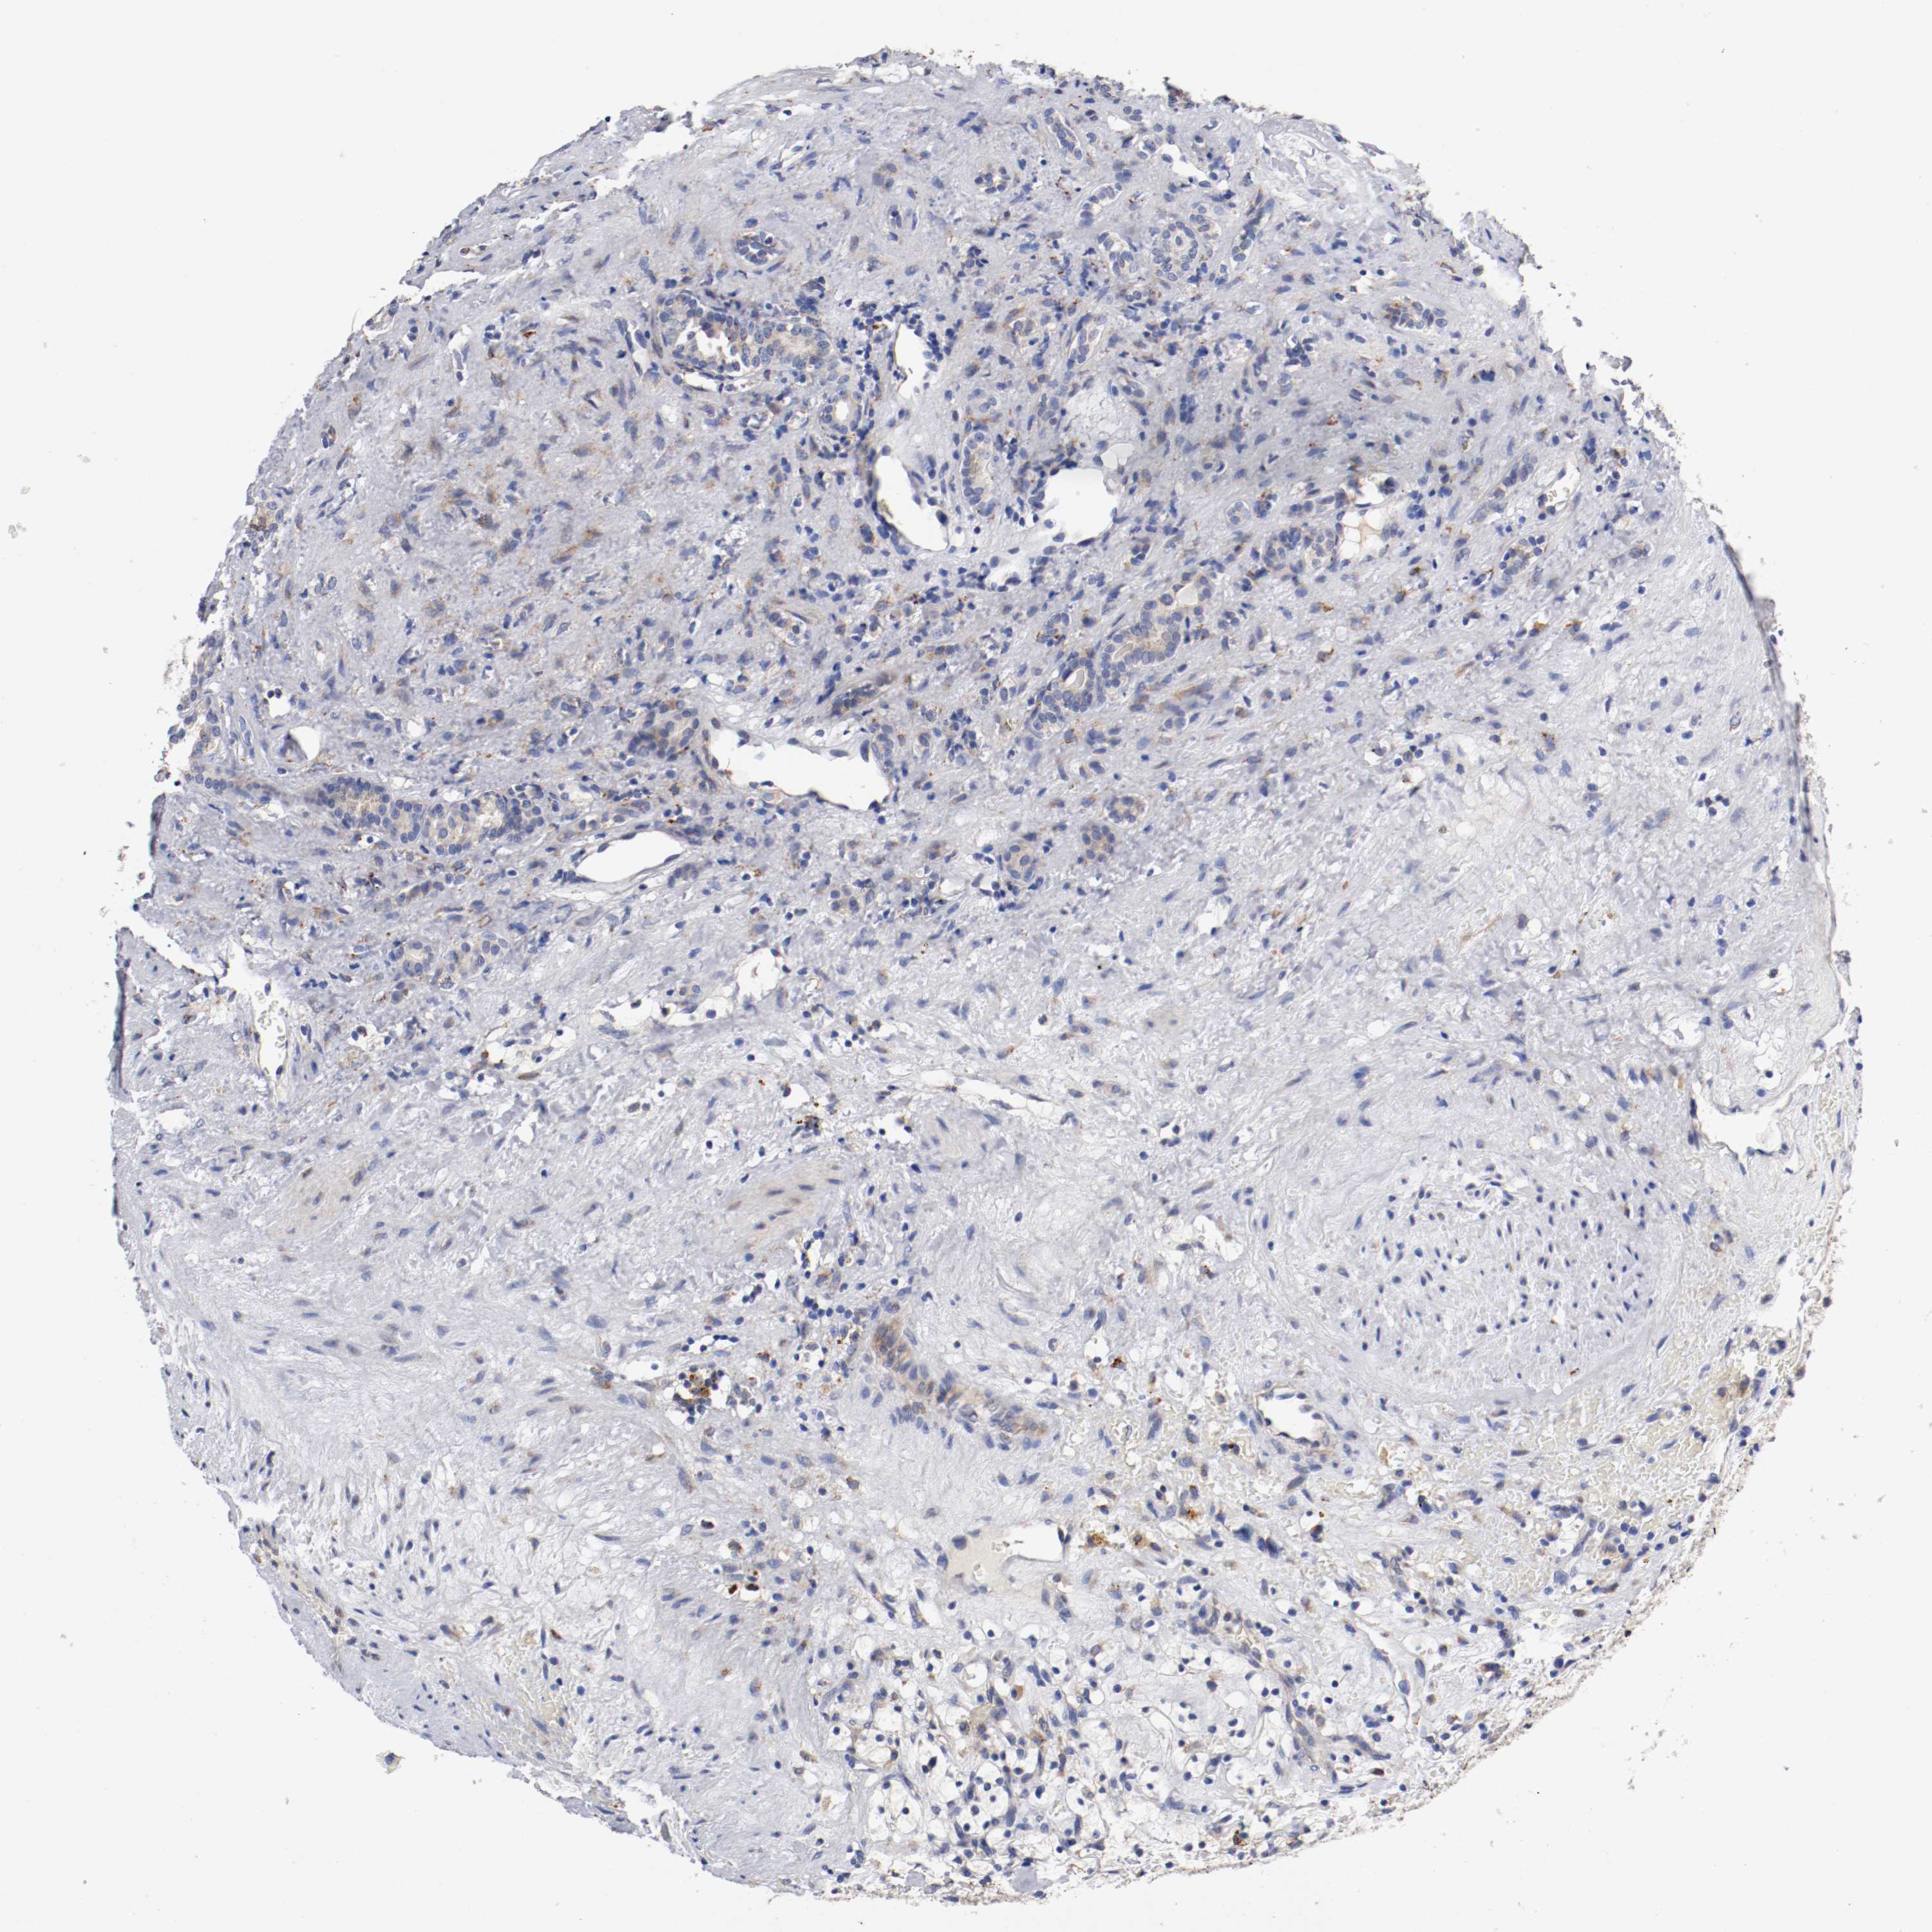

KIDNEY RENAL CLEAR CELL CARCINOMA (VALIDATION) - Interactive survival scatter ploti

The Survival Scatter plot shows the clinical status (i.e. dead or alive) for all individuals in the patient cohort, based on the same data that underlies the corresponding Kaplan-Meier plots. Patients that are alive at last time for follow-up are shown in blue and patients who have died during the study are shown in red.

The x-axis shows the expression levels (FPKM) of the investigated gene in the tumor tissue at the time of diagnosis. The y-axis shows the follow-up time after diagnosis (years). Both axes are complimented with kernel density curves demonstrating the data density over the axes. The top density plot shows the expression levels (FPKM) distribution among dead (red) and alive patients (blue). The right density plot shows the data density of the survived years of dead patients with high and low expression levels respectively, stratified using the cutoff indicated by the vertical dashed line through the Survival Scatter plot. This cutoff is automatically defined based on the FPKM cutoff that minimizes the p-score. The cutoff can be changed by dragging the vertical line or by entering a cutoff value in the square labeled "Current cut-off".

Under the Survival Scatter plot the p-score landscape (black curve; left axis) is shown together with dead median separation (red curve; right axis). Dead median separation is the difference in median mRNA expression between patients who have died with high and low expression, respectively. It is calculated as follows: median FPKM expression of dead patients with high expression - median FPKM expression of dead patients with low expression. This is intended to aid the user in visually exploring custom cutoffs and the associated p-scores and dead median separation.

Individual patient data is displayed and can be filtered by clicking on one or more of the category buttons on the top of the page. Categories describing expression level and patient information include: high, low, alive, dead, female, male and tumor stages. The scale of the x-axis can be toggled between linear and log-scale by clicking on the "x log" button. Mouse-over function shows TCGA ID, patient information and mRNA expression (FPKM) for each patient.

& Survival analysisi

Kaplan-Meier plots summarize results from analysis of correlation between mRNA expression level and patient survival. Patients were divided based on level of expression into one of the two groups "low" (under cut off) or "high" (over cut off). X-axis shows time for survival (years) and y-axis shows the probability of survival, where 1.0 corresponds to 100 percent.

TRAF2 is not prognostic in Kidney Renal Clear Cell Carcinoma (validation)

: 13.68

Average pTPM 17.4

Number of samples 100